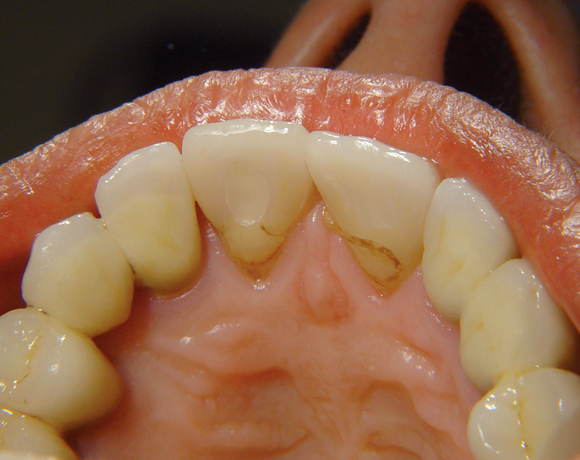

Bei diesem Patientenfall musste nach Neuüberkronung der Frontzähne eine Wurzelbehandlung erfolgen. Um der Gefahr aus dem Weg zu gehen, dass die neue Krone abbricht, da sehr wenig eigene Zahnrestsubstanz nach der endodontischen Behandlung übriggeblieben war, wurde der Zahn nachträglich mit einem Dentinpost versorgt.